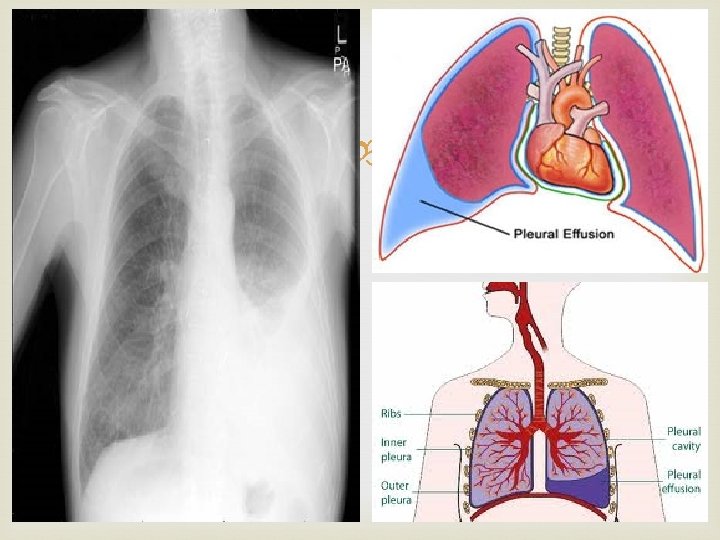

Pleural Effusion The pleural space normally contains 5 to 10 m. L of clear fluid any condition that increases the production of the fluid (e. g. , inflammation, malignancy, congestive heart disease) or impairs the drainage of the fluid (e. g. , collapsed lung) results in the abnormal accumulation of fluid, called a pleural effusion. The presence of 300 m. L of fluid in the costodiaphragmatic recess in an adult is sufficient to enable its clinical detection. The clinical signs include decreased lung expansion on the side of the effusion, with decreased breath sounds and dullness on percussion over the effusion.